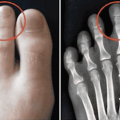

Указательный палец длиннее других? Вот что это может сказать о Вашем характере